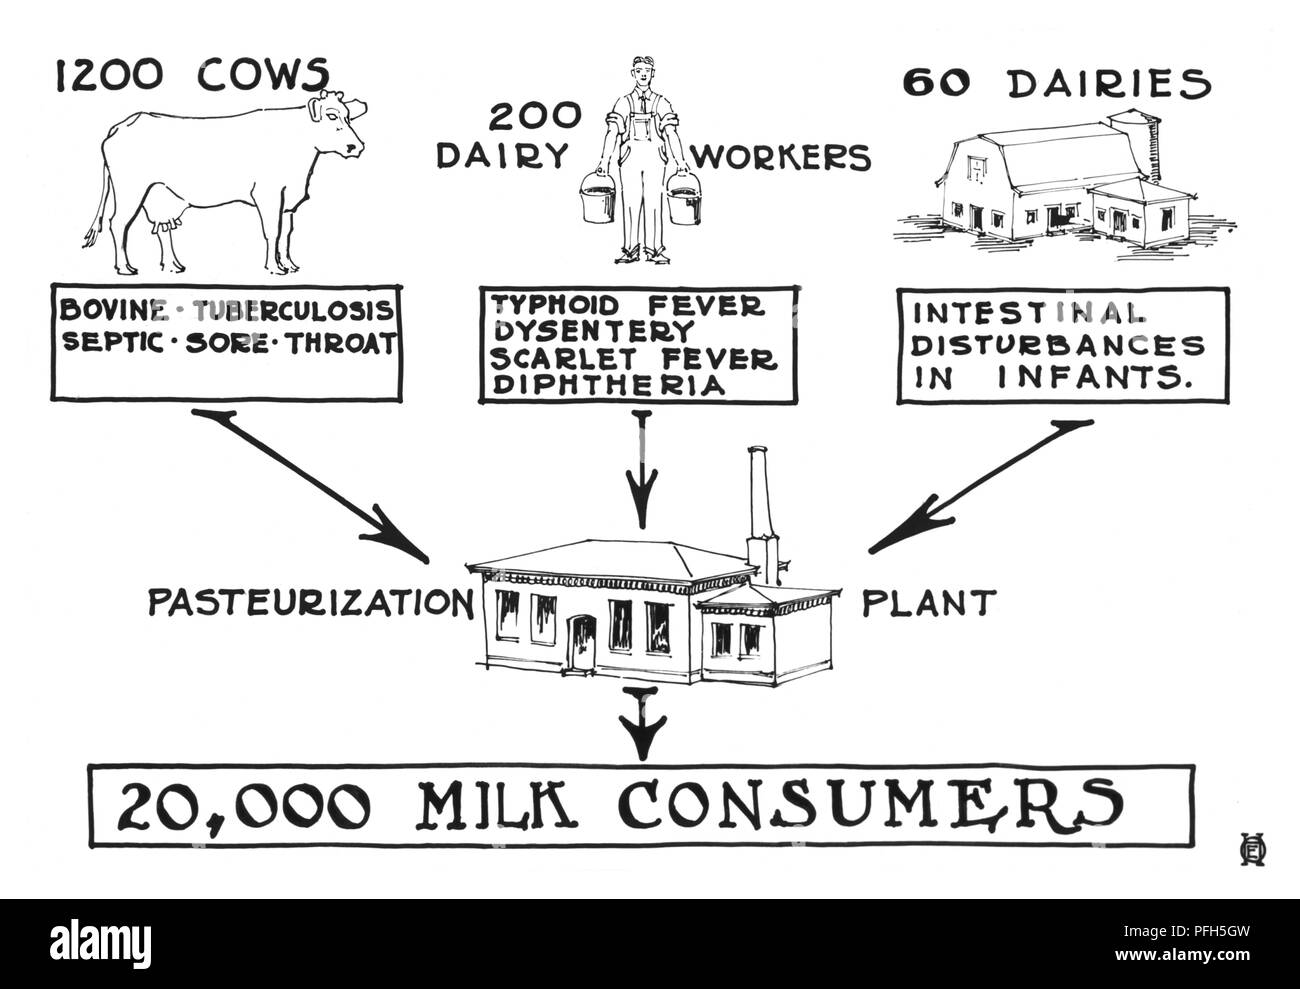

RMPFH5GW–Potenziali fonti di latte crudo di contaminazione, Minnesota Department of Health, migliorate digitalmente schema, 1925. Immagine cortesia di centri per il controllo delle malattie (CDC) / Minnesota Department of Health, R.N. Libreria Barr, Bibliotecari Melissa Rethlefsen e Marie Jones. ()